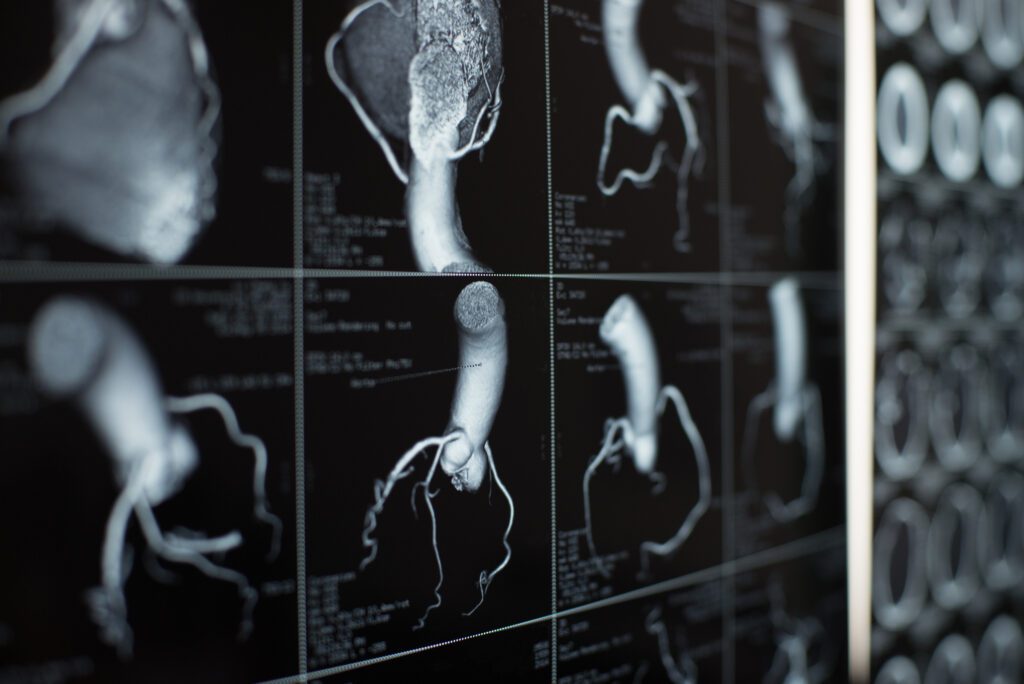

A coronary computed tomography angiography (CCTA) is a non-invasive method of imaging the coronary vessels, the arteries that supply blood to the heart.

A coronary computed tomography angiography (CCTA) is a non-invasive method of imaging the coronary vessels, the arteries that supply blood to the heart. Compared to conventional angiography, coronary CT angiography requires very little preparation, no recovery time and yields highly specific results. A CT calcium score, to measure mature atherosclerotic plaque, is performed at the same time.